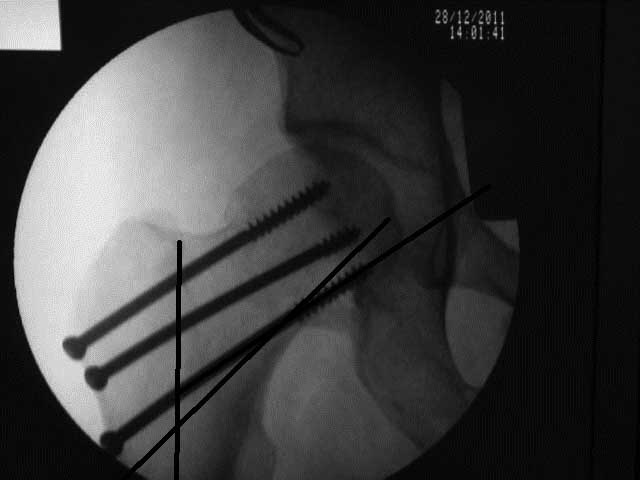

результат, в конце операции.

Винты немного вертикальнее провести и было бы красивее.

>Винты немного вертикальнее провести и было бы красивее

Правильная техника фиксации - это три параллельных каннюлированных винта под углом 130 -135 градусов к диафизу, не ниже уровня малого вертеля. Проведенные ниже вертела винты с бОльшим углом (более вертикальные) в 20% осложнялись подвертельными переломами бедра. Ближе к кортикальному слою винты с длинным контактом резбовой части, а также каннюлирванные механически лучше, чем сплошные. Расположение винтово - в в виде V т.е. один внизу по калькару и два сверху-спереди и сзади.